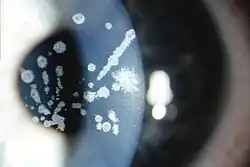

Die Granuläre Hornhautdystrophie Typ II ist eine sehr seltene angeborene Form der granulären Hornhautdystrophie mit unregelmäßig geformten, gut abgegrenzten granulären Ablagerungen zentral oberflächlich im Stroma der Hornhaut und fortschreitender Minderung der Sehschärfe.[1]

Granuläre Hornhautdystrophie Typ II, unterschiedlich große krümelartige Trübungen im Hornhautstroma, konfluierend zu streifigen und gezackten Formen